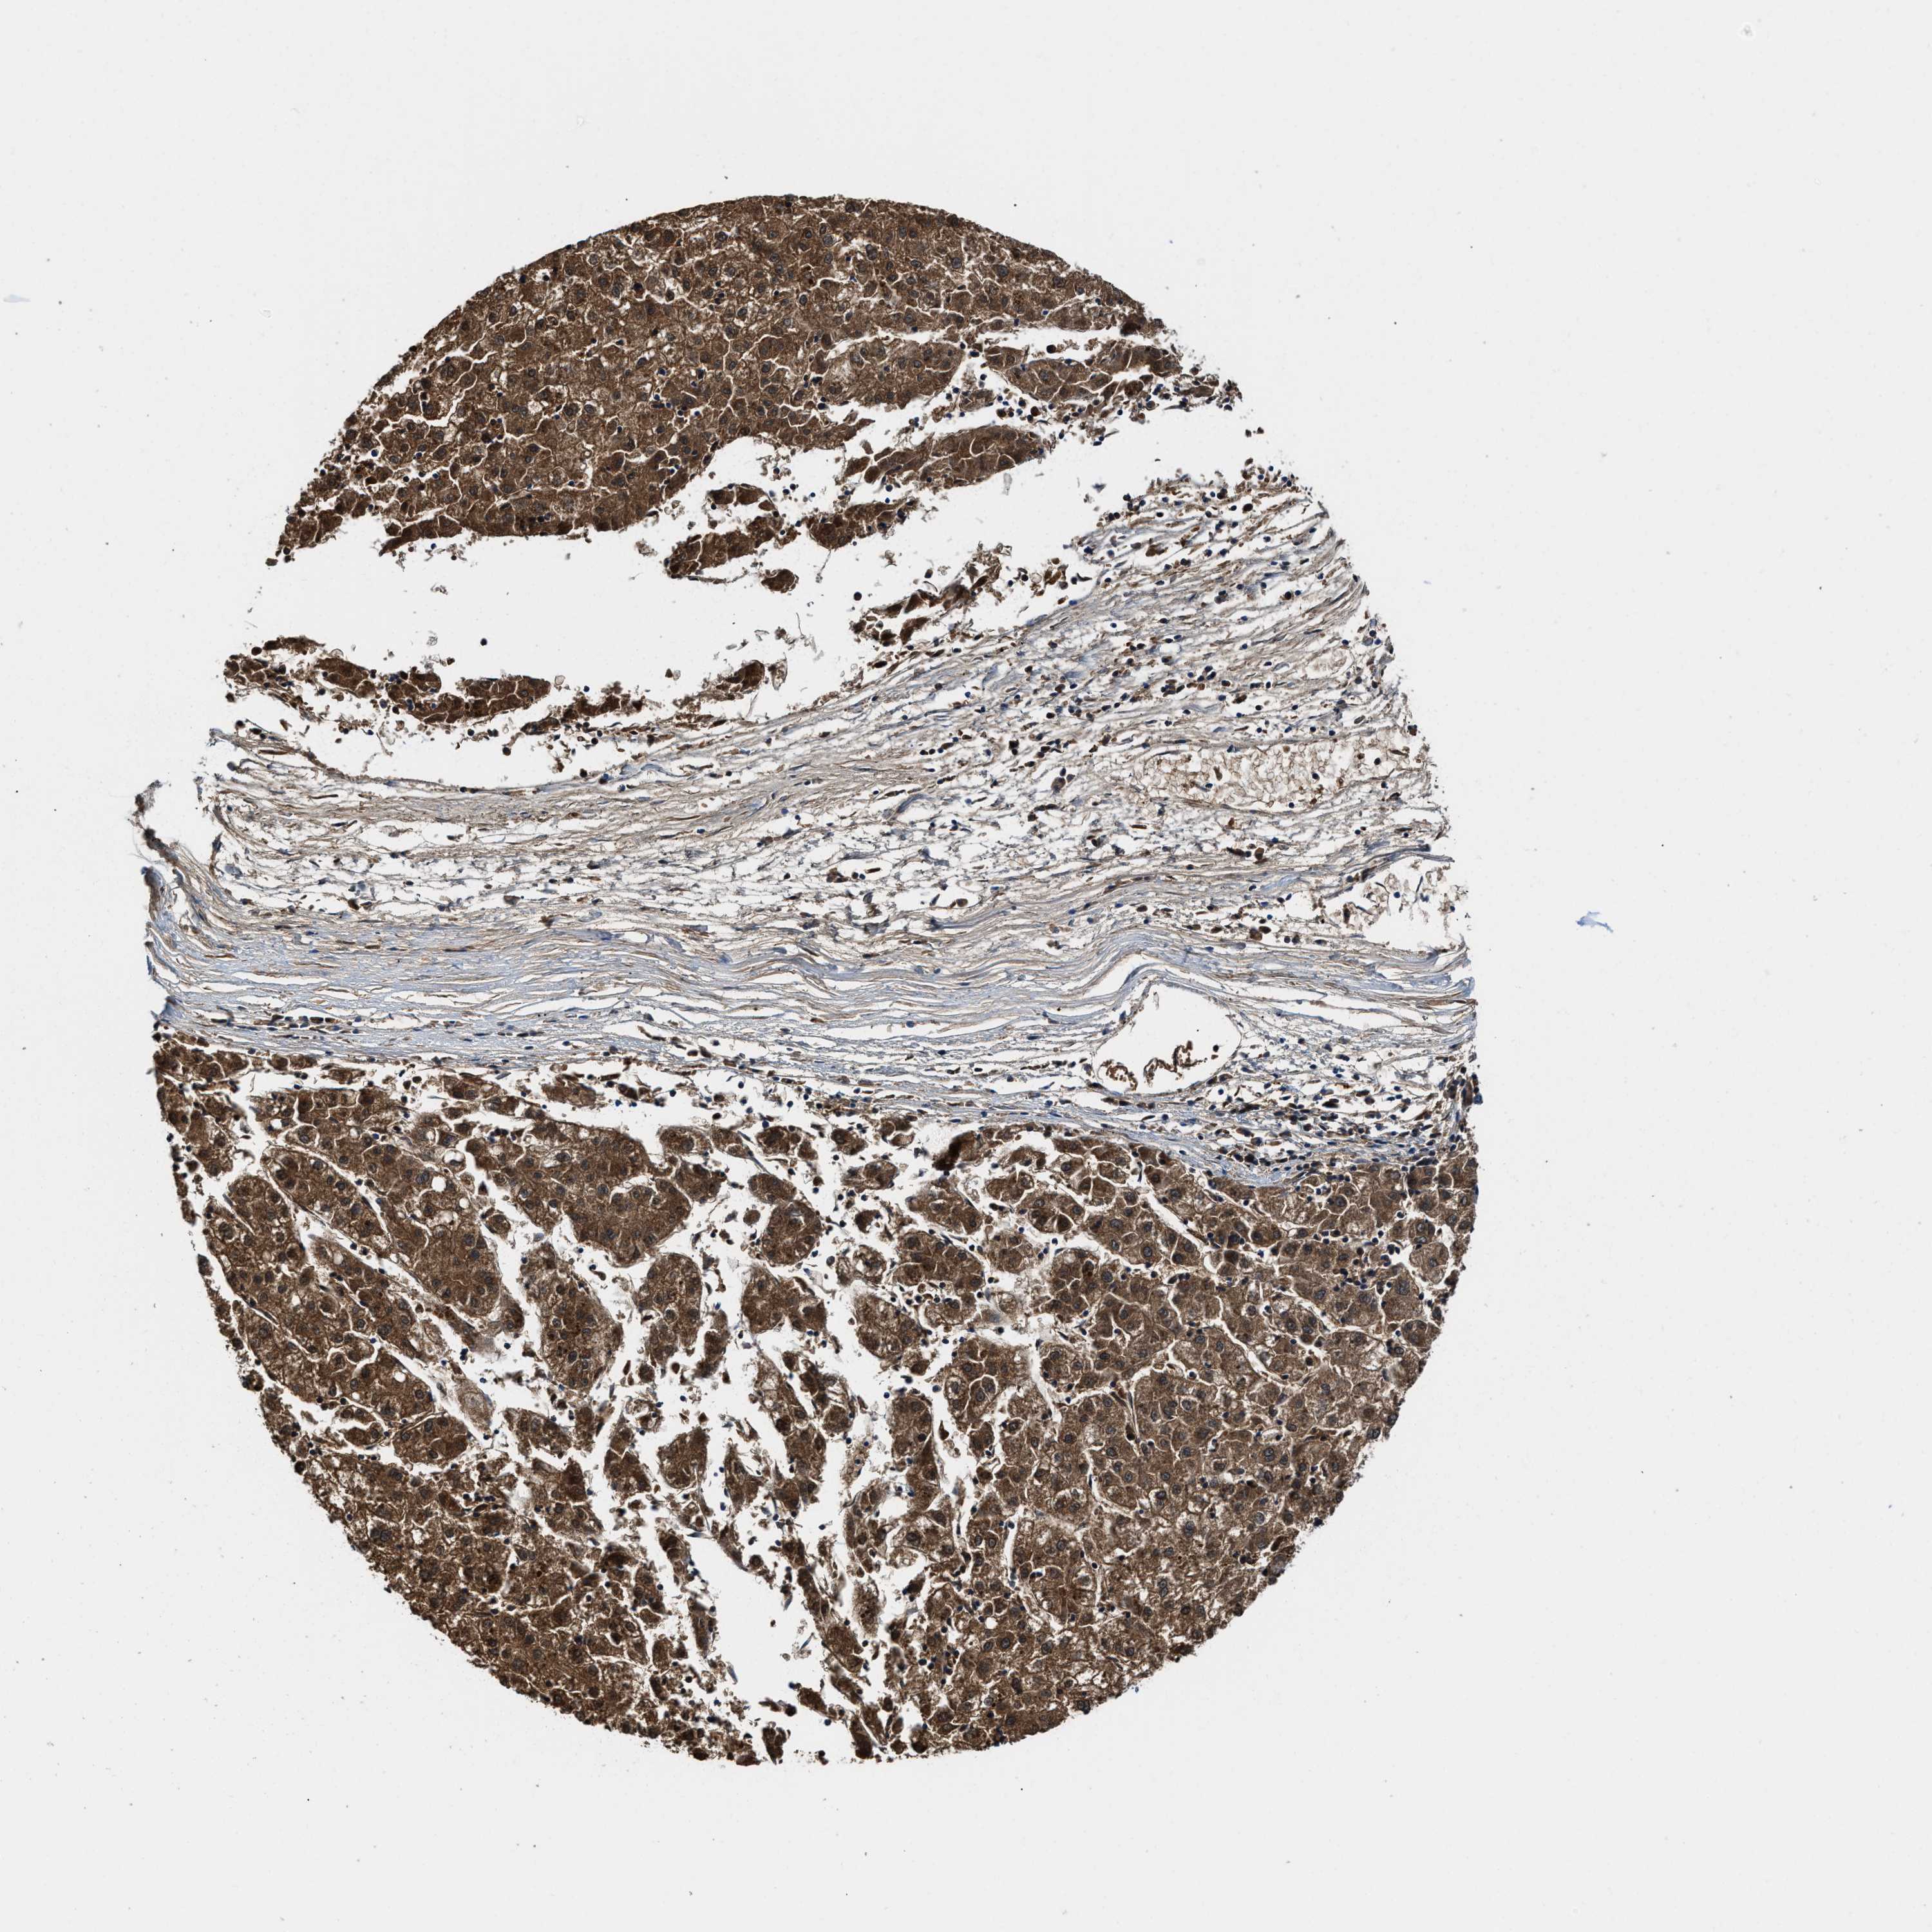

LIVER CANCER - Protein expressioni

A mouse-over function shows sample information and annotation data. Click on an image to view it in a full screen mode. Samples can be filtered based on level of antibody staining by selecting one or several of the following categories: high, medium, low and not detected. The assay and annotation is described here.

Note that samples used for immunohistochemistry by the Human Protein Atlas do not correspond to samples in the TCGA dataset.

Antibody stainingi

Antibody staining in the annotated cell types in the current human tissue is reported as not detected, low, medium, or high, based on conventional immunohistochemistry profiling in selected tissues. This score is based on the combination of the staining intensity and fraction of stained cells.

Each image is clickable and will lead to virtual microscopy that enables deeper exploration of all samples and also displays staining intensity scores, fraction scores and subcellular localization as well as patient and tissue information for each sample.

Antibody HPA008399

Antibody HPA017017

Antibody CAB015221

Staining

High

Medium

Low

Not detected

Intensity

Strong

Moderate

Weak

Negative

Quantity

>75%

75%-25%

<25%

None

Location

Nuclear

Cytoplasmic/membranous

Cytoplasmic/membranous,nuclear

Cholangiocarcinoma

Carcinoma, Hepatocellular, NOS